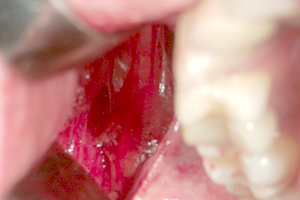

写真で見る「バッカルファットを除去する様子」

③ バッカルファット

の確認

④ バッカルファット

の露出

バッカルファットパット直下に至ると、卵黄色の薄い膜に包まれたバッカルファットを目視できます。直視下において、除去すべき脂肪を一塊に除去します。